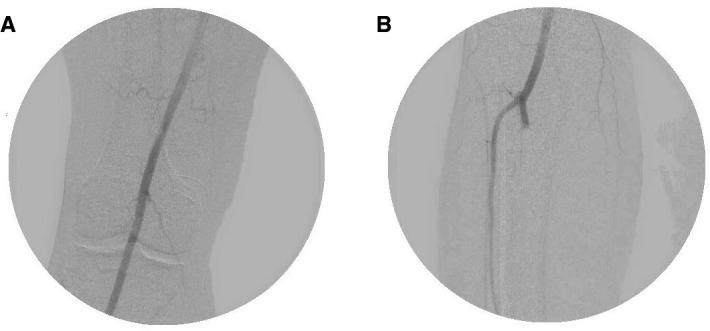

COVID-19 is caused by the SARS-CoV-2, and its presentation ranges from mild upper respiratory illness to critical disease including acute respiratory distress syndrome and multiorgan dysfunction. While it was initially believed to primarily target the respiratory system, numerous studies have demonstrated it to cause a hypercoagulable state that predisposes to arterial and venous thrombosis. We present a case where a patient with COVID-19 developed acute lower limb ischaemia due to arterial thrombosis in the setting of full-dose enoxaparin, followed by heparin infusion protocol. The patient developed recurrent ischaemia despite thrombolysis in addition to anticoagulation, and eventually required open thrombectomy before making a full recovery.

COVID-19 由 SARS-CoV-2 引起,其表现从轻症上呼吸道疾病到包括急性呼吸窘迫综合征和多器官功能障碍在内的重症不等。虽然最初认为它主要针对呼吸系统,但许多研究表明它会导致高凝状态,从而容易发生动脉和静脉血栓形成。我们提出了一个病例,一名 COVID-19 患者在接受全剂量依诺肝素的情况下发生了动脉血栓形成导致急性下肢缺血,随后开始肝素输注方案。尽管进行了溶栓和抗凝治疗,但患者仍反复发生缺血,最终需要进行开放血栓切除术才能完全康复。